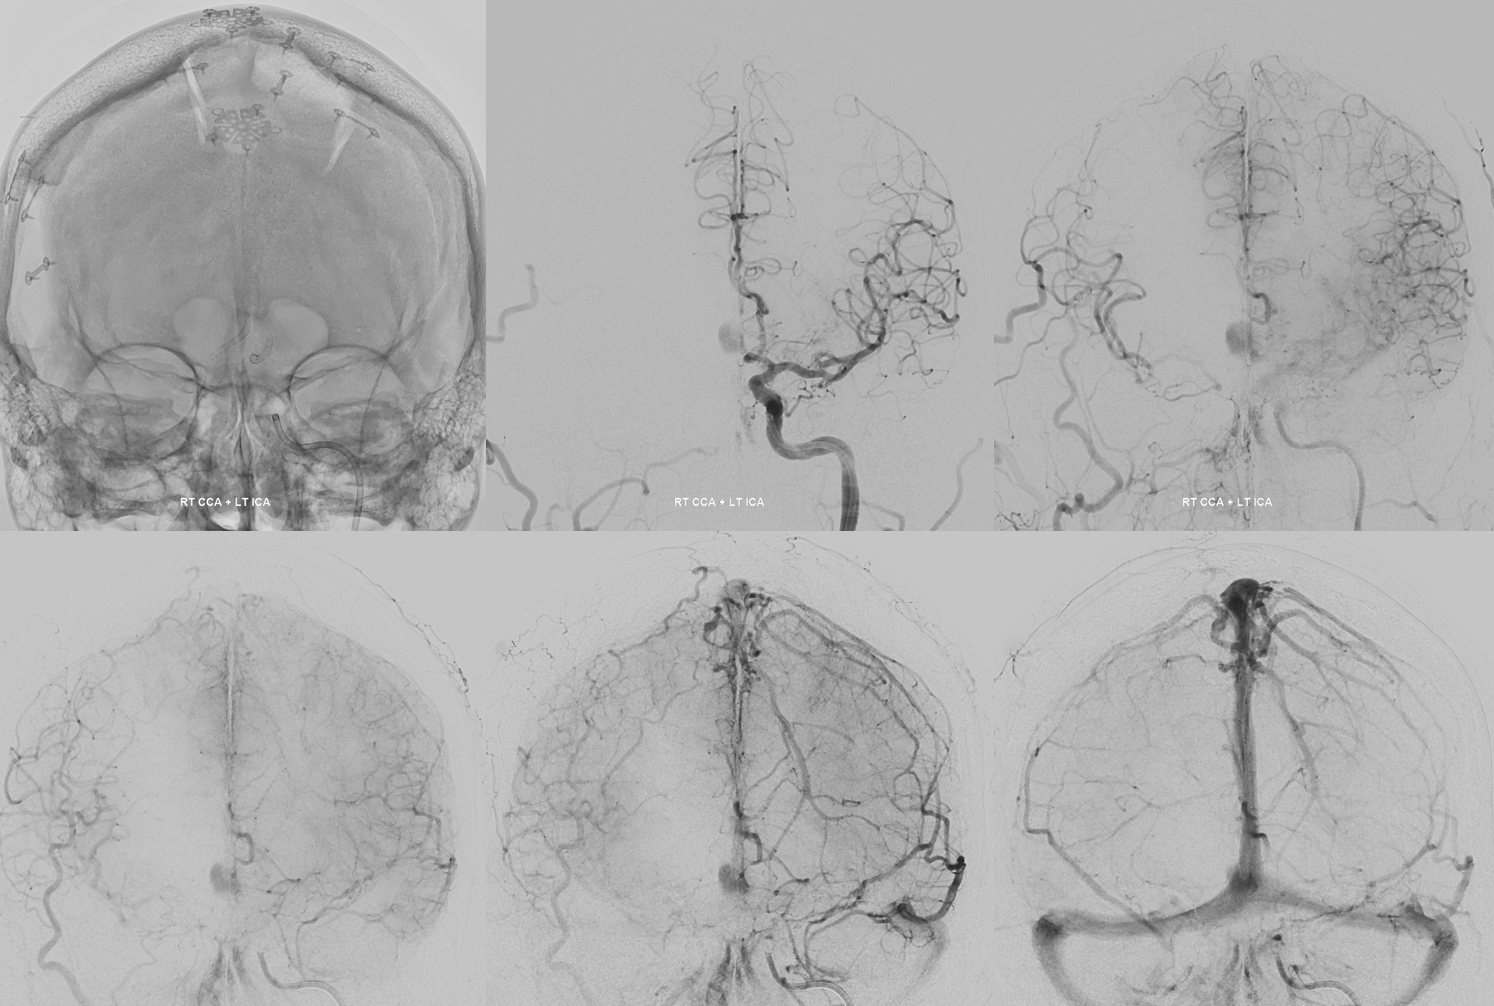

Giant ACOM

More problems? Yes

So far, we have a giant mostly thrombosed ACOM aneurysm with adjacent edema, a chronically occluded right cervical ICA, and right ACA dependent on the ACOM flow… Not easy

Spins are good

A secondary reconstruction and detailed analysis is better. What does arrow point to?

Spin

A better unsubtracted spin